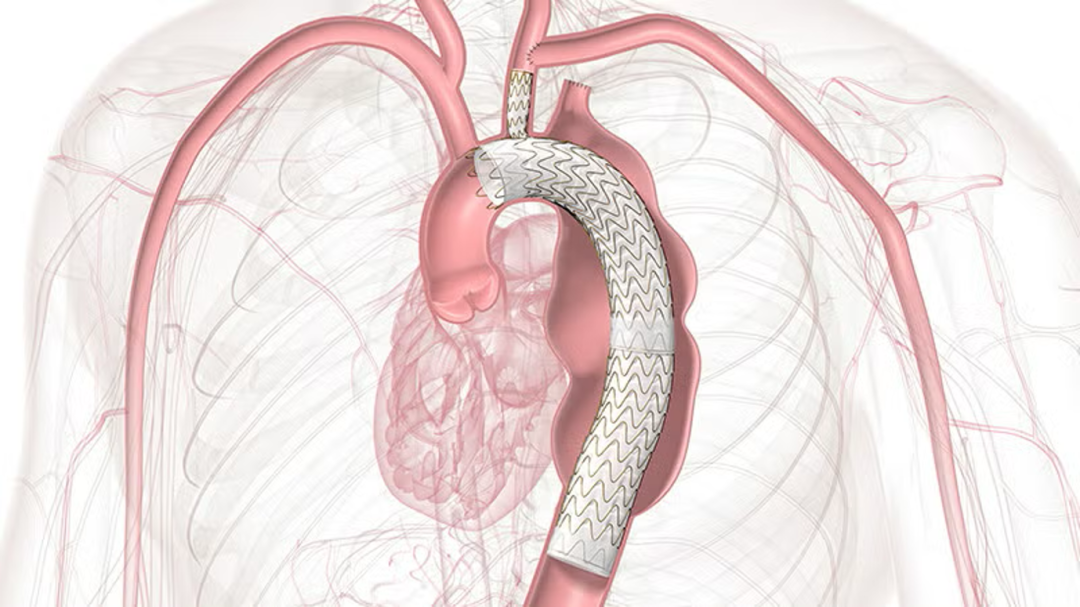

主动脉弓部病变的腔内治疗,长久以来被视为血管外科的“雷区”。在TEVAR(胸主动脉腔内修复术)中,为了获得足够的锚定区(Landing Zone)而覆盖弓部分支(如左锁骨下动脉LSA),往往伴随着卒中、截瘫及上肢缺血的风险。然而,随着TAG®Thoracic Branch Endoprosthesis (TBE) 在2024年底获得中国台湾TFDA批准,以及其在美国相继获得Zone 2(2022年)及Zone 0/1(2025年6月)的FDA批准,这一困境正在被打破。

TBE支架的出现,解决了“等待时间”与“解剖适应”之间的矛盾。

★ 结构设计

TBE并非单一的直管状支架,而是一个由主动脉主体(Aortic Component)、分支组件(Side Branch Component)和主动脉延长段(Aortic Extender)组成的系统。

内部端口(Internal Portal): 主体支架上的特殊设计,允许分支支架在此固定,实现密封。

柔软性: 分支设计具有极佳的柔顺性,以适应弓部的弯曲血流动力学。